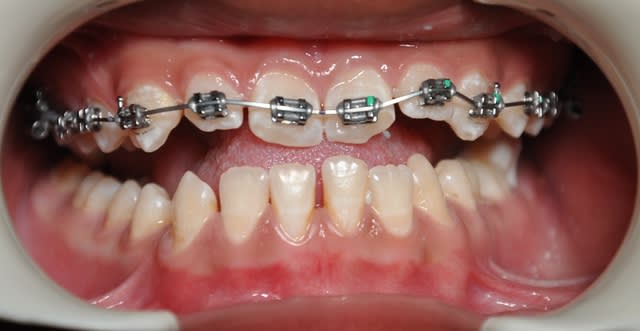

voici la première étape

Dsc 0002 crlur4 - Eugenol

Dsc 0006 h1ilt3 - Eugenol

Dsc 0001 qxvuke - Eugenol

Dsc 0005 pcikt2 - Eugenol